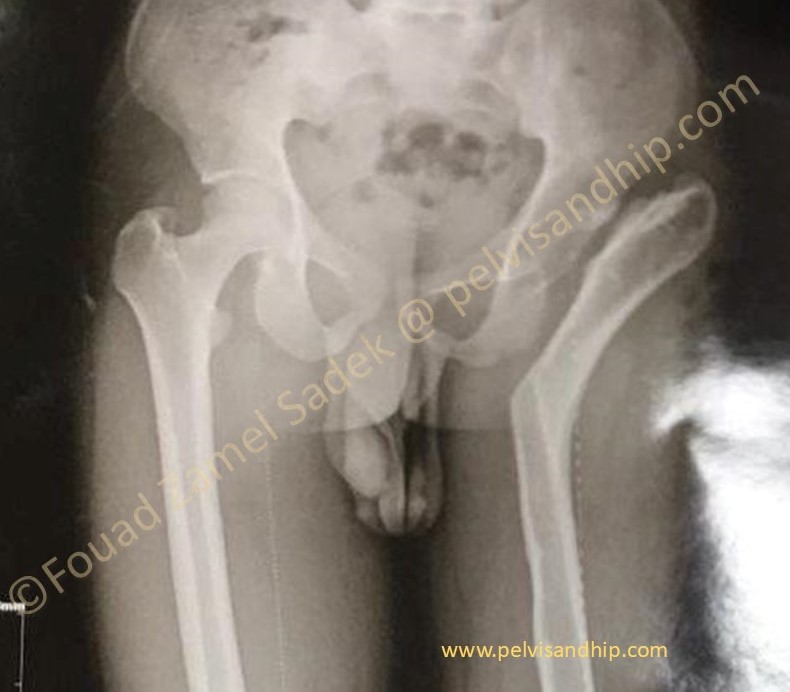

Case 1: dysplastic hip with secondary osteoarthritis with proximal migration and shortening with a resulting pelvic obliquity (please click on the picture)